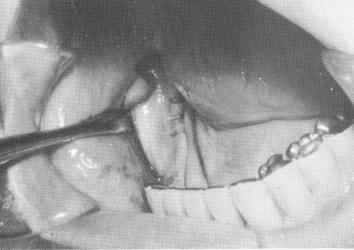

Rubber base or Neoplex impression material is then mixed and placed inside the tray, and the tray is positioned over the site and held for 10 minutes. The tray may be removed, so that the impression may be checked for accuracy, and then replaced, but this is not necessary. A full lower alginate impression of all the prepared abutments as well as of the entire acrylic tray with the rubber base impression is taken. After the alginate has set, the entire mass is removed intact (Fig. 12-51) and the tissues sutured

Fig. 12-51. An elastic (Neoplex by Surgident or Coeflex rubber base by Coe) impression of the bone is taken and "picked up" with a full mouth alginate impression that also includes the prepared abutment teeth.

Fig. 12-52. The tissue wound is sutured.

2 Elastic impression of jaw bone taken & picked with alginate impression

3 Tissue wound in mandibular arch sutured